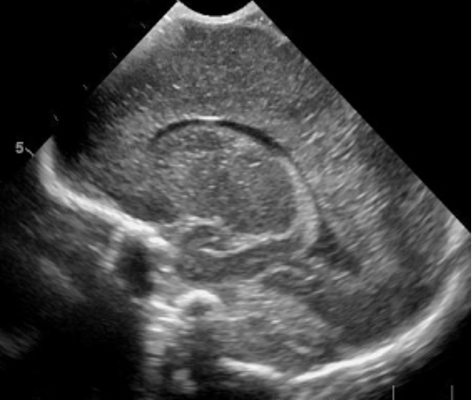

Neonatology Grade 0 PVL 2 Image